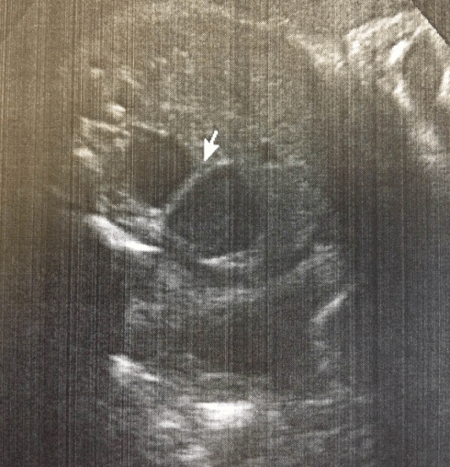

A full-term 2610g male neonate was admitted to the intensive care unit (NICU) with an antenatal history significant for a “double bubble” detected during the second trimester ultra sound examination (Fig. 1). A presumed diagnosis of duodenal stenosis/atresia was made with further karyotyping and anomaly scan showing no abnormalities. The antenatal imaging performed in the third trimester re-confirmed the findings of a double-bubble with no other anomalies being identified. Born at 38 +2/7 weeks, with APGAR scores of 7 and 9, the neonate had mild fullness of the right upper quadrant on clinical exam but no palpable mass. A supine abdominal x-ray revealed a dilated small bowel loop in the right upper quadrant with distal bowel gas, which was interpreted as a possible mega duodenum due to obstruction at that site consistent with the antenatal “double bubble” finding (Fig. 2). Patient then underwent an upper gastrointestinal series (UGI), which initially revealed no evidence of gastric outlet and duodenal obstruction or malrotation. However, subsequent delayed films showed of a space-occupying lesion in the right upper quadrant with a characteristic displacement of small bowel loops. Its subsequent opacification on delayed films was suggestive of a duplication cyst (Fig. 3). No evidence of bowel obstruction was seen. A post-natal ultrasound was not considered necessary in view of the findings on the UGI series.

Figure 3: Delayed UGI films showing a duplication cyst of the jejunum |